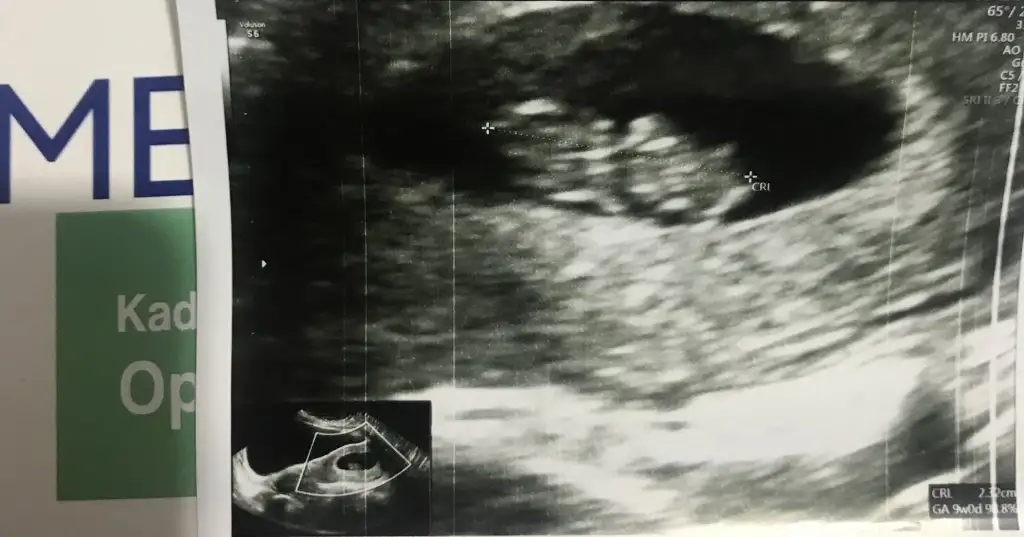

Kızlar selamlar,uzun zamandır giremedim okudum şükür bitti şimdi,sıkıntısı olanlarım sıkıntısını gidersin Rabbim en kısa vakitte, bebişlerimizi sağlıkla sıhhatle kucağınıza almayı nasip etsin🤲🏻 Bulantı her hamilelikte farklı okur derlerdi gerçekten öyle oğlumda 5 ay kustum bunda ara ara 2 ay şükür iyiyim 10.hafta bitti tam.zencefil içerikli takviye kullanıyorum folik asit var içerisinde belki o da etkili oldu bilemiyorum.Bebeğinin cinsiyetini öğrenen arkadaşlar hayırlı olsun ben de çok merak ediyorum.Bugün yüzük testi yaptık😂daire çizdi yüzük kız oluyor sanırım ultrason fotoğrafını atsam bana da yorum yapar mısınız🥰

Ultrason karındna bu arada